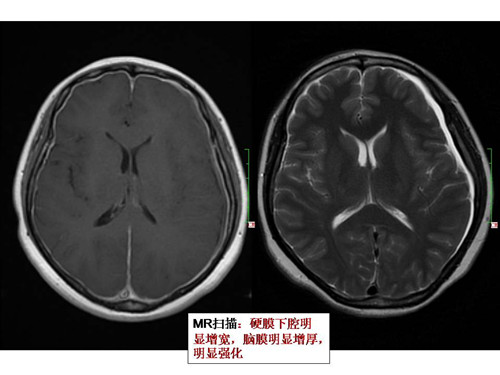

• 您知道反復(fù)頭暈嘔吐需做MRI檢查嗎?

您了解MRI嗎?您知道當(dāng)反復(fù)頭暈嘔吐時需要進行MRI檢查嗎? 42歲的張女生被反復(fù)頭暈、時而嘔吐等癥狀纏繞半年,并且在站立時病狀會加重,躺下時才能減緩。 憂心忡忡的張女士在家人的陪同下曾到醫(yī)院進行過頭顱CT等檢…